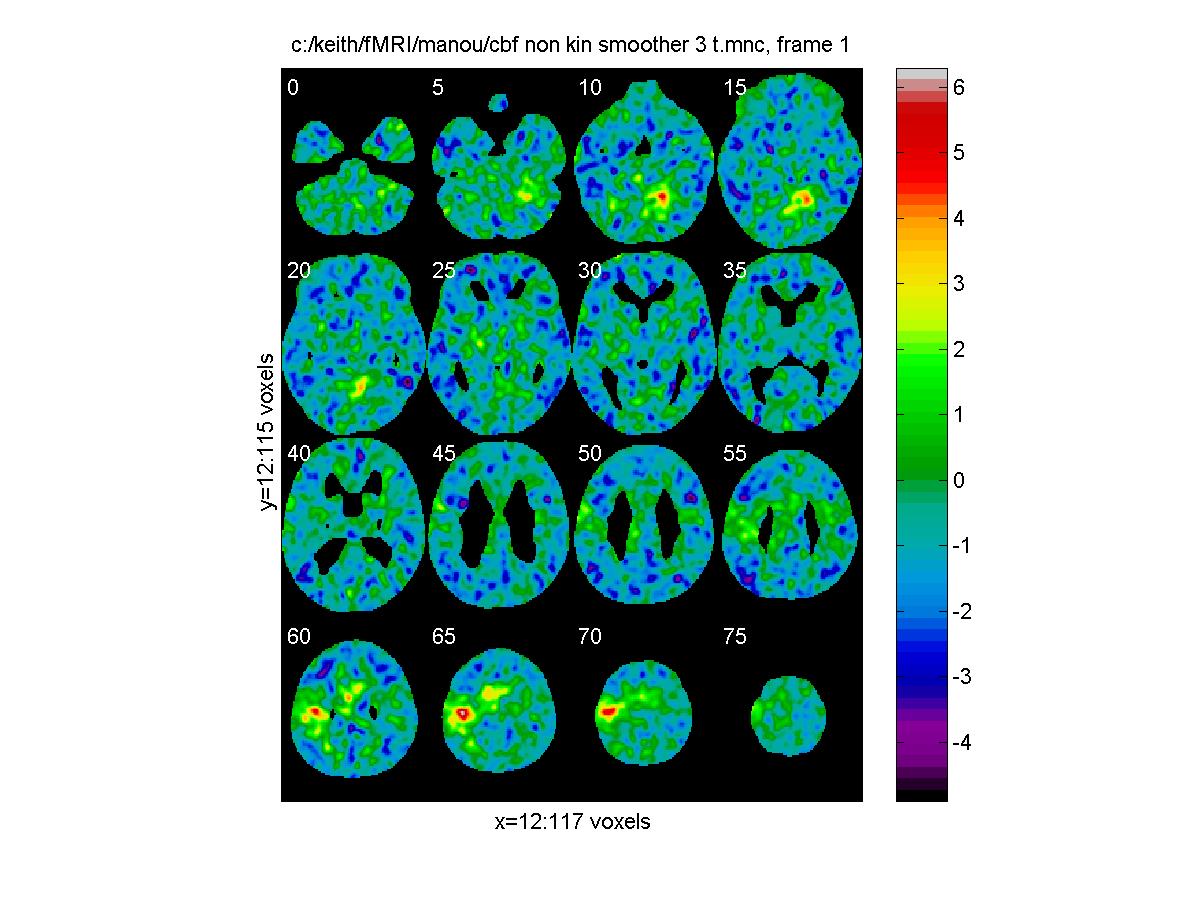

T statistic = effect / standard error:

clf;

view_slices('c:/keith/fMRI/manou/cbf_non_kin_smoother_3_t.mnc',mask,0.65,[0:5:79])

![[Click to enlarge image]](figs_pet_tn/fignormt.jpg)